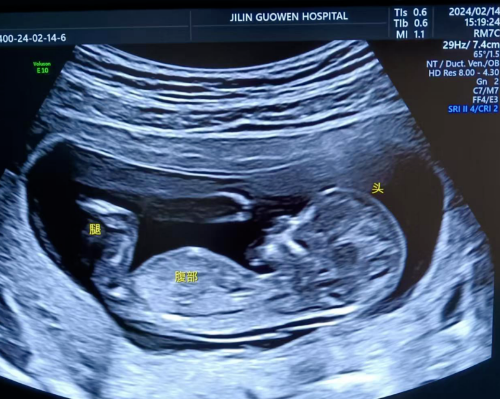

品質國文 | 寶媽看過來!胎兒NT彩超免費檢查

寶媽看過來!胎兒NT彩超免費檢查長春國文醫(yī)院支持國家優(yōu)生優(yōu)育政策,回饋寶媽,NT彩超檢查免費。那么,什么是NT檢查呢? 閱讀量:1455